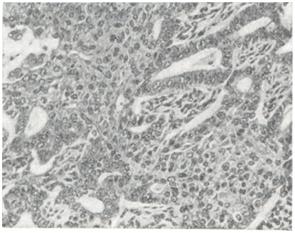

Аденоакантома (adenoacanthoma; греческое aden—железа, akantha — шип + -oma) — злокачественная опухоль с признаками диморфной дифференцировки по железистому и плоскоклеточному типу.

В большинстве случаев аденоакантома относят к аденокарциномам различных органов с явлениями плоскоклеточной метаплазии (повидимому, ложной) железистого эпителия (смотри Рак), иногда с образованием роговых масс, вплоть до формирования раковых «жемчужин». Аденоакантома встречается в пищеводе, обычно в зоне пищеводно-желу-дочного перехода, в желудке, желчном пузыре, поджелудочной железе, прямой кишке, анальном канале, влагалище, матке, яичниках (рис. 1.), коже, потовых железах. Макроскопически аденоакантома практически не отличима от картины железистого рака соответствующего органа. Микроскопически в опухоли наряду со структурой аденокарциномы обычно обнаруживают ряд фаз гетероплазии железистого эпителия в многослойный плоский. Оба структурных компонента аденоакантомы с различными признаками дифференцировки эпителия бывают, расположены в одних и тех же участках и интимно связаны между собой.

Рис. 1.

Гиперплазия фолликулов в аденоидной ткани.